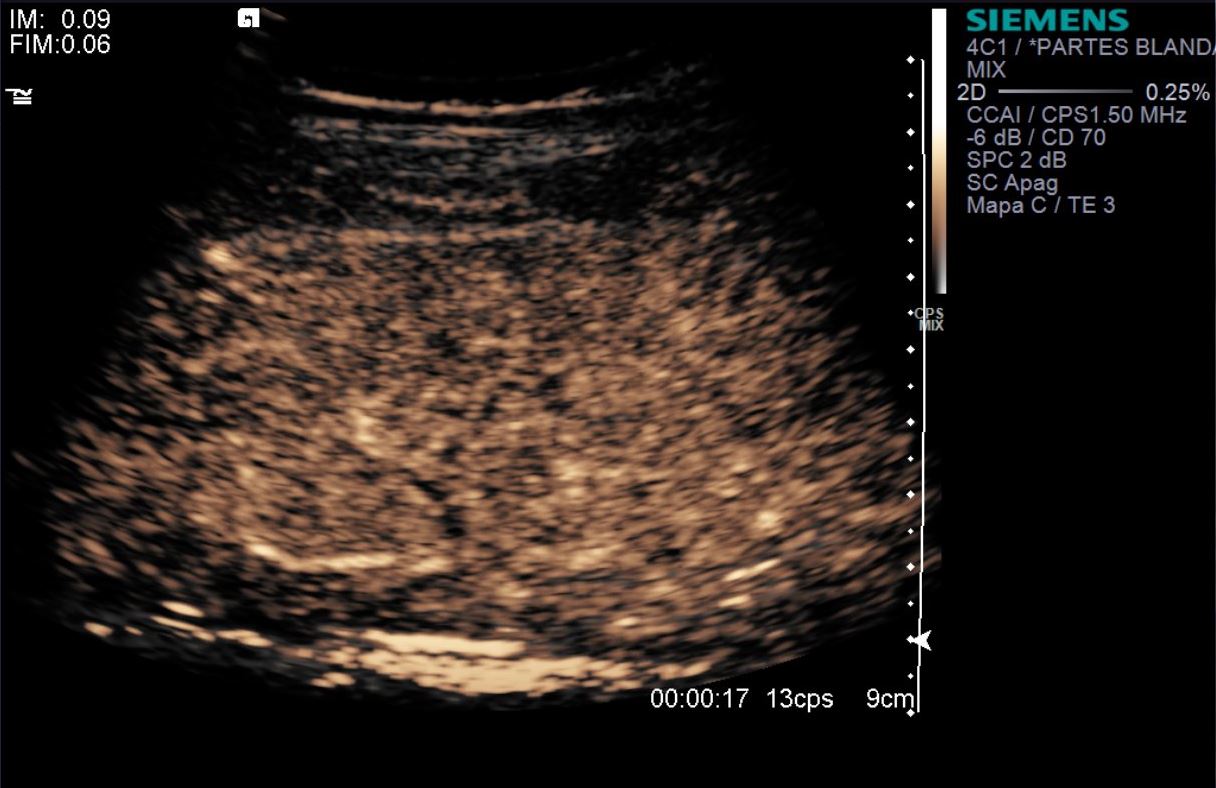

eco con contraste IV